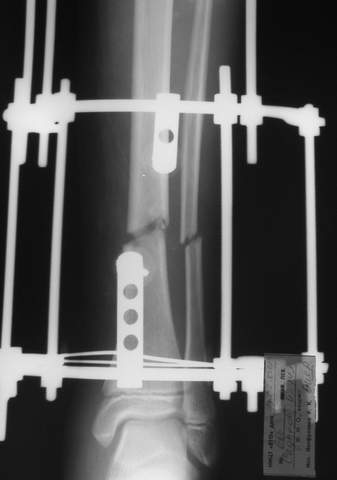

В аттачтах №№ 1 и 2 - примеры, когда 2 кольца не позволили послеоперационно

исправить смещение фрагментов большеберцовой (по ширине и вальгусное).

А казалось бы (#2) - поиграй на штангах и все влетит.

Оперировал не я

:-)

1

1a